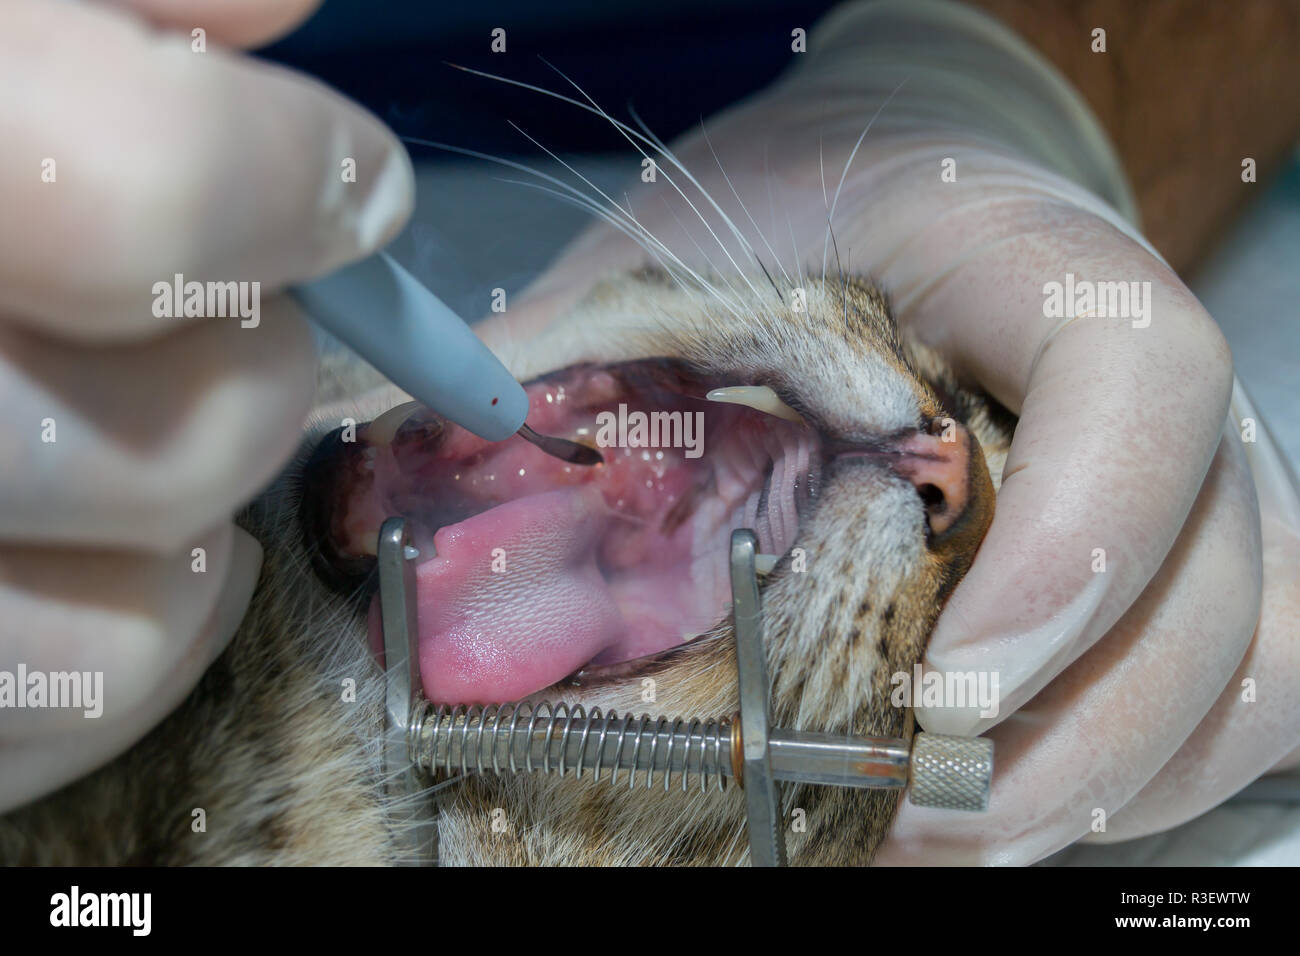

Katze mit tonsillitis, Mandeln entfernen mit elektrokauter, orale Chirurgie in Haustiere Stockfotohttps://www.alamy.de/image-license-details/?v=1https://www.alamy.de/katze-mit-tonsillitis-mandeln-entfernen-mit-elektrokauter-orale-chirurgie-in-haustiere-image225906674.html

Katze mit tonsillitis, Mandeln entfernen mit elektrokauter, orale Chirurgie in Haustiere Stockfotohttps://www.alamy.de/image-license-details/?v=1https://www.alamy.de/katze-mit-tonsillitis-mandeln-entfernen-mit-elektrokauter-orale-chirurgie-in-haustiere-image225906674.htmlRFR3EX7E–Katze mit tonsillitis, Mandeln entfernen mit elektrokauter, orale Chirurgie in Haustiere

Katze mit tonsillitis, Mandeln entfernen mit elektrokauter, orale Chirurgie in Haustiere Stockfotohttps://www.alamy.de/image-license-details/?v=1https://www.alamy.de/katze-mit-tonsillitis-mandeln-entfernen-mit-elektrokauter-orale-chirurgie-in-haustiere-image225906410.html

Katze mit tonsillitis, Mandeln entfernen mit elektrokauter, orale Chirurgie in Haustiere Stockfotohttps://www.alamy.de/image-license-details/?v=1https://www.alamy.de/katze-mit-tonsillitis-mandeln-entfernen-mit-elektrokauter-orale-chirurgie-in-haustiere-image225906410.htmlRFR3EWX2–Katze mit tonsillitis, Mandeln entfernen mit elektrokauter, orale Chirurgie in Haustiere

Katze mit tonsillitis, Mandeln entfernen mit elektrokauter, orale Chirurgie in Haustiere Stockfotohttps://www.alamy.de/image-license-details/?v=1https://www.alamy.de/katze-mit-tonsillitis-mandeln-entfernen-mit-elektrokauter-orale-chirurgie-in-haustiere-image225906377.html

Katze mit tonsillitis, Mandeln entfernen mit elektrokauter, orale Chirurgie in Haustiere Stockfotohttps://www.alamy.de/image-license-details/?v=1https://www.alamy.de/katze-mit-tonsillitis-mandeln-entfernen-mit-elektrokauter-orale-chirurgie-in-haustiere-image225906377.htmlRFR3EWTW–Katze mit tonsillitis, Mandeln entfernen mit elektrokauter, orale Chirurgie in Haustiere